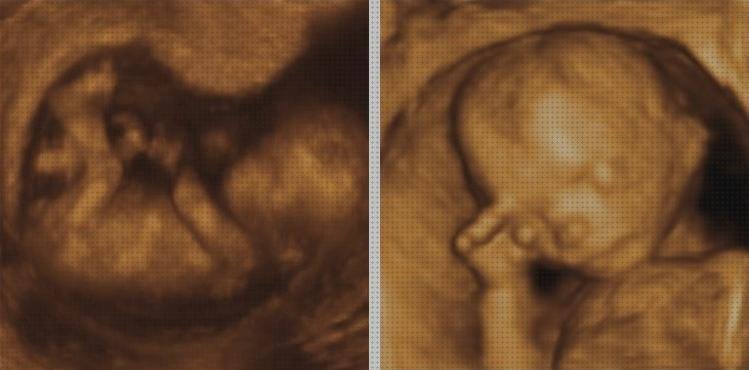

La ecografía es una manera de valoración médica, en la que las imágenes se constituyen por el uso de ultrasonidos. Los ultrasonidos, al cruzar las diferentes construcciones devuelven “ecos” de distintas amplitudes según sean los órganos atravesados, produciendo imágenes que habilitan analizar su propia volumen, manera, cabida, función, etc…

se emplea para el diagnóstico y mando de varias patologías o circunstancias particulares: Control del estorbo, ecografía abdominal, ecocardiografía, ecografía ginecológica y urológica, ecografía de las extremidades, ecografía ocular, ecografía de las arterias del cervical, etc…

también se utiliza como guía para secar abscesos (colecciones líquidas en órganos internos) o para hacer biopsias. Solo la presencia de tito, aire u obesidad extrema interfieren con su propia manejo ideal. La ecografía doppler es un modelo especial de ecografía, que agrega la oportunidad de evaluar el movimiento de la sangre, por lo que se emplea para analizar arterias, venas y la vascularización de los órganos.

Técnica consiste en ubicar un transductor o tubo que produce los ecos sobre la piel (con un gel acuoso de interfase), y se representan las imágenes en una monitora. Estas fotos se registran para su propia estudio posterior, y para que resulte constancia de los hallazgos. En el estudio ginecológico o prostático, la sonda se insertará por el ano o la vagina para el correcto formación de estos órganos.

La ecografía o ultrasonografía es un método de imagen médica que hace uso de los sonidos (vibraciones en el sentido de efluvio del bucle) de mayor continuidad para conseguir fotos de dentro del cuerpo. El sonido se proyecta de un modo característico según el tejido con el que ofende y según su propio espacio en humor. Un programa informático traduce la información recibida a fotos que se representan en una sola televisor, y pueden imprimirse o recordar en vídeo.

Más tarde, los aparatos se fueron sofisticando y nació la ecografía-doppler, que es una manera ultrasónica que deja estudiar el flujo de los diferentes vasos mediante el registro de la onda de la pulsación y la determinación de su fuerza.